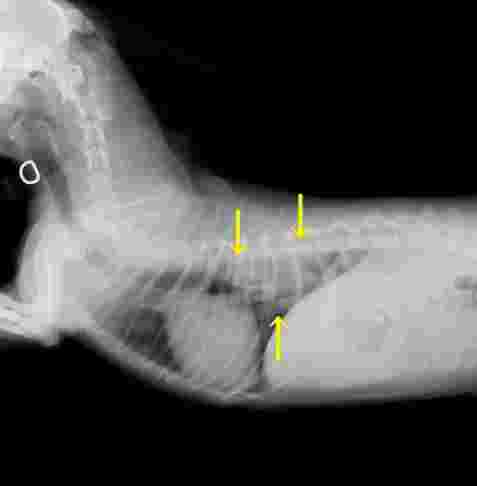

診斷過程通常需要多管齊下。獸醫可能會先聽診,然後建議做X光或超音波。X光是最基本的工具,可以看肺部的陰影變化。但如果腫瘤很小,X光可能看不出來,這時就需要進階檢查如CT掃描。

| 影像學檢查 | X光、超音波 | 查看肺部有無異常陰影 |